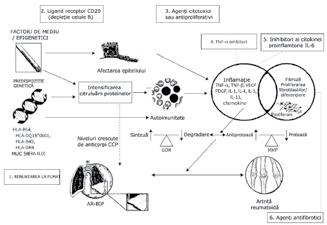

INTERFERONUL DE TIP Ielement cheie in etiopatogenia lupusului eritematos sistemic (LES).

lnterfero nul de ti p I este o citokina im porta nta , atat in imun itatea in nascuta, cat $i in cea do bandita; perturba rile celor do ua ti puri de imun itate contr ibuie la pro ces ul de autodistrugere din LES, un pro ces ci clic in ca re interfero nul de ti p I are un ro l centr al.

ROLUL INTERFERON I IN LES

Ca raspuns la interferonul de tip I, celulele sistemului imunitar atat inascut, cat $i dobandit eliberea za o cascada de citokine proinf lamatorii $i autoanticorpi, formand acid nucleic care contine complexe imune ce pot initia leziuni tisulare $i afectarea organelor 7

B REG = B regulatory; DAMP = damage-associated molecular pattern; IFN = interferon; mDC = myeloid dendritic cell; NK = natural kille; PAMP = pathogen-associated molecular pattern; pDC = plasmacytoid dendritic cell; SLE = systemic lupus erythematosus; TC cytotoxic T; T H = T helper; T H 17 = T helper 17; T REG = regulatory T.

Referinte: 1. R6nnblom L, Leonard D. lnterleron pathway in SLE: one key to unlocking the mystery of the disease. Lupus Sci Med. 2019;6(1):e000270; 2. Buyon JP, Cohen R Merrill JT, et al A highlight from the LUPUS 2014 meeting: eight great ideas. Lupus Sci M 20152(1):e000087; 3. Liu Z. Davidson A Taming lupus - a new understanding of pathogenesis is leading to clinical advances. Nat M 201218(6):871-882; 4. Chan VS, Nie YJ, Shen N, Van S Mok MY, Lau CS Distinct roles of myeloid and plasmacytoid dendritic cells in systemic lupus erythematosus. Autoimmun Rev. 2012;11(12):890897; 5. Menon M, Blair PA, Isenberg DA, Mauri C. A regulatory feedback between plasmacytoid dendritic cells and regulatory B cells is aberrant in systemic lupus erythematosus. Immunity. 201644(3):683-697; 6. West PK, Viengkhou B, Campbell IL, et al. Microglia responses to interleukin-6 and type I interferons in neuroinflammatory disease. Glia_ 2019;67(10):1821-1841